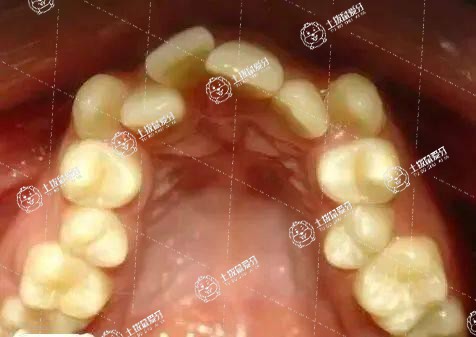

有智齒大多可以矯正矯正牙齒的,在進(jìn)行矯正的時(shí)候,最好拍片檢查一下智齒的位置,如果位置不正,影響到矯正的效果,最好將繼續(xù)拔除。

患者可以通過(guò)佩戴牙套的方式來(lái)矯正牙齒,智齒是人的第三磨牙,如果智齒生長(zhǎng)比較正常,不影響到鄰近的牙齒,也不影響牙齒矯正,不需要拔除。在矯正的過(guò)程中要注意口腔的清潔和衛(wèi)生,避免吃生冷寒涼的食物。

正畸一般需要做術(shù)前全口曲面斷層片,能準(zhǔn)確看出是否有智齒。如果智齒存在,盡量在正畸前拔除,因?yàn)檎菍㈩M骨內(nèi)所有牙齒排列整齊,達(dá)到完美的咬合關(guān)系。如果正畸治療后出現(xiàn)智齒萌出,可能對(duì)正畸效果有影響。在智齒萌出的過(guò)程中,前牙可能會(huì)受到壓力,牙齒的咬合位置會(huì)發(fā)生變化。因此,在正畸治療前應(yīng)盡量拔除智齒,以免造成正畸效果或正畸治療后復(fù)發(fā)。

需要看智齒的傾斜程度,有必要的話也可以考慮拔除智齒,然后再進(jìn)行鑲牙或者移牙來(lái)進(jìn)行矯正,具體要咨詢醫(yī)生,由醫(yī)生根據(jù)牙齒的實(shí)際情況作出適合的相應(yīng)方案。期間要注意口腔的衛(wèi)生情況。